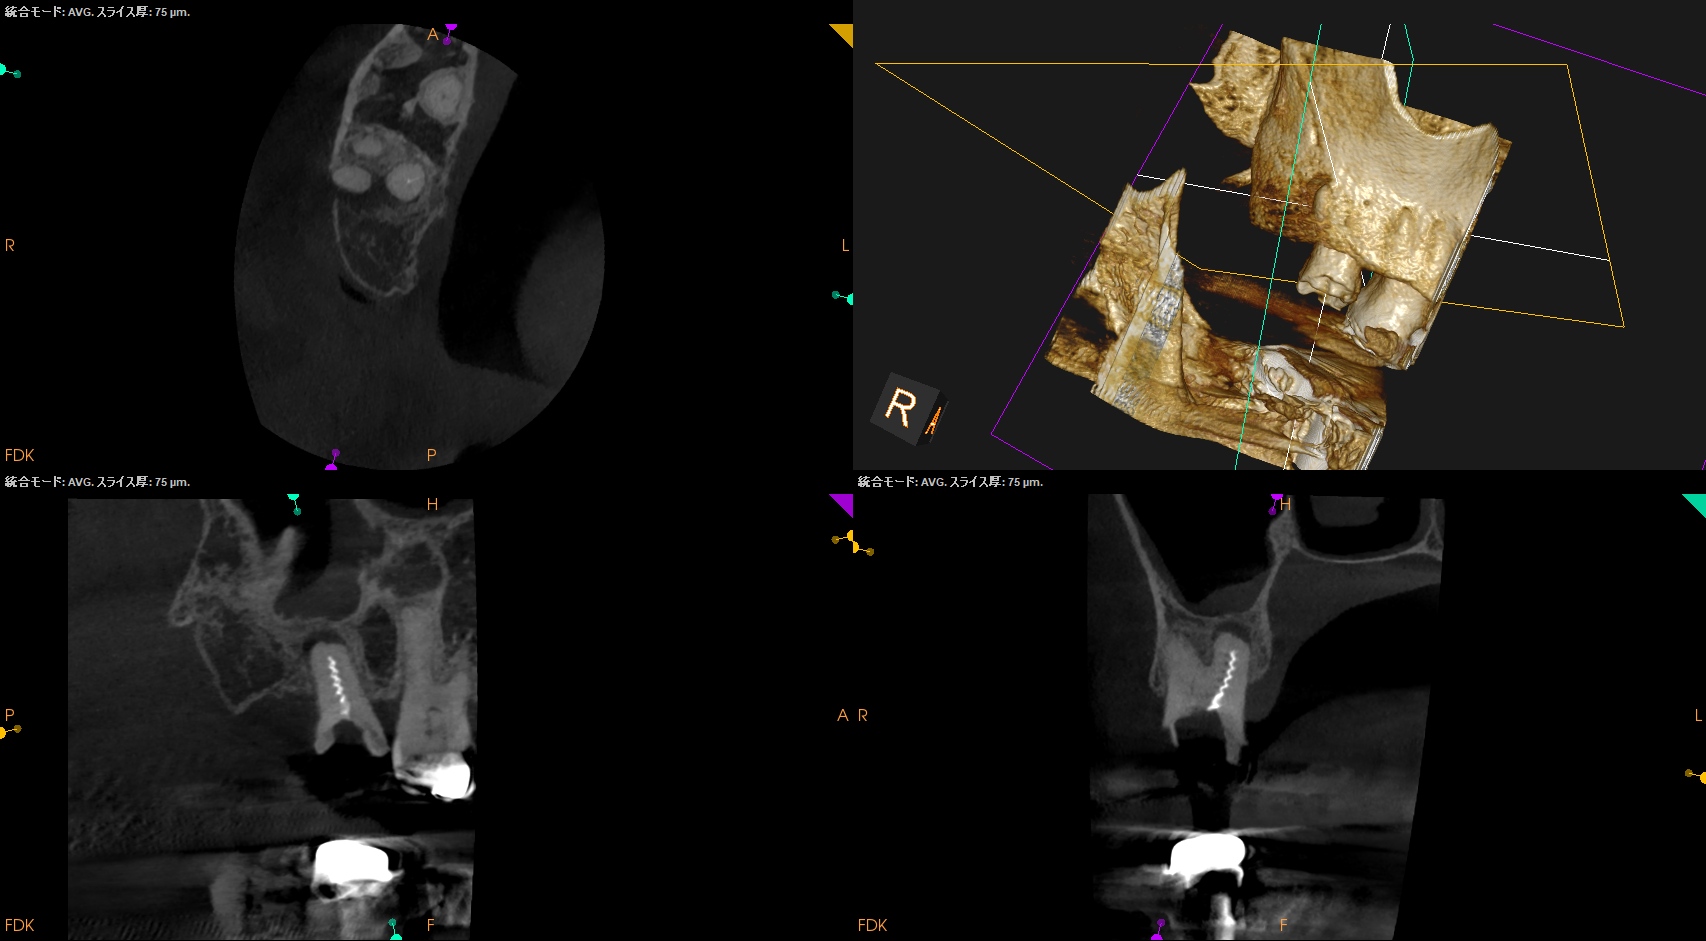

Pre-op Endo test(2026.3.9)

#2

MB

DB

P

B

MB, DB, Pともに石灰化している。

DBは根管口自体がどこにあるか?判然としない。

予測では、

MBのGutta Percha Pointの近傍にそれはありもしかすると石灰化しているかもしれない。

その際は3mm~4mm程度削合する必要があるかもしれない。

Pre-op Endo Diagnosis(2026.3.9)

Pulp Dx: Previously initiated therapy

Periapical Dx: Symptomatic apical peridontitis

Recommended Tx: Re-RCT